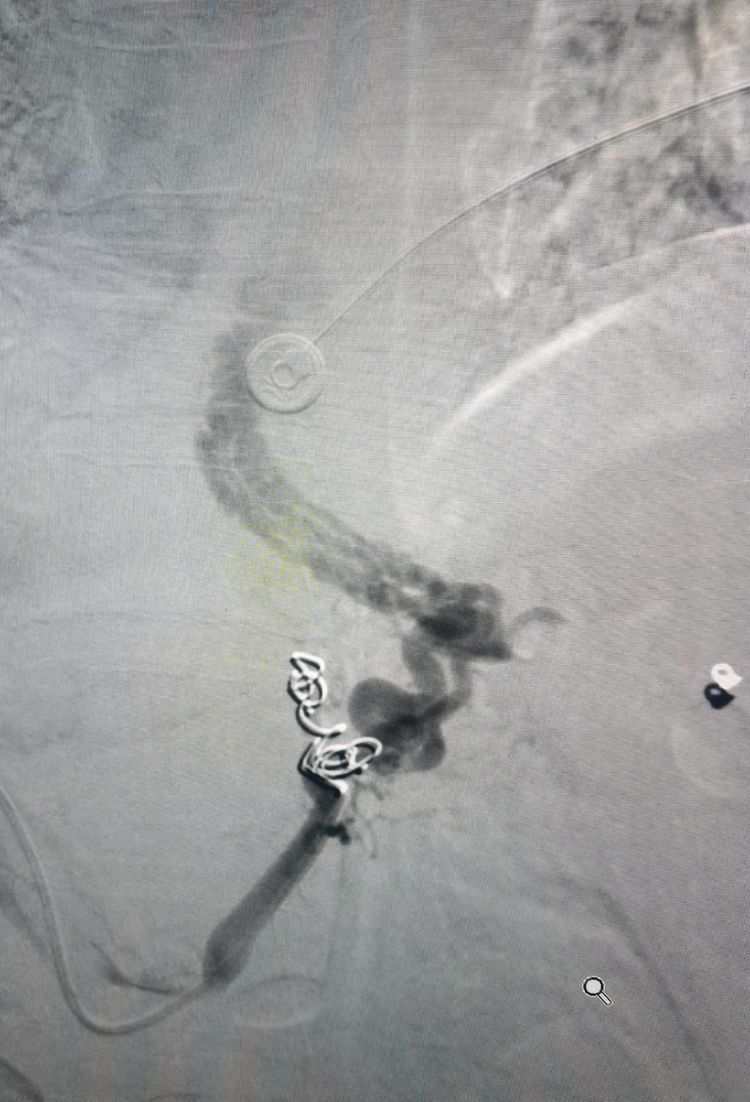

立即经导管进行栓塞:弹簧圈+医用胶。

栓塞结束后再次造影:食管胃底曲张静脉消失。术后患者未出现呕血、黑便。